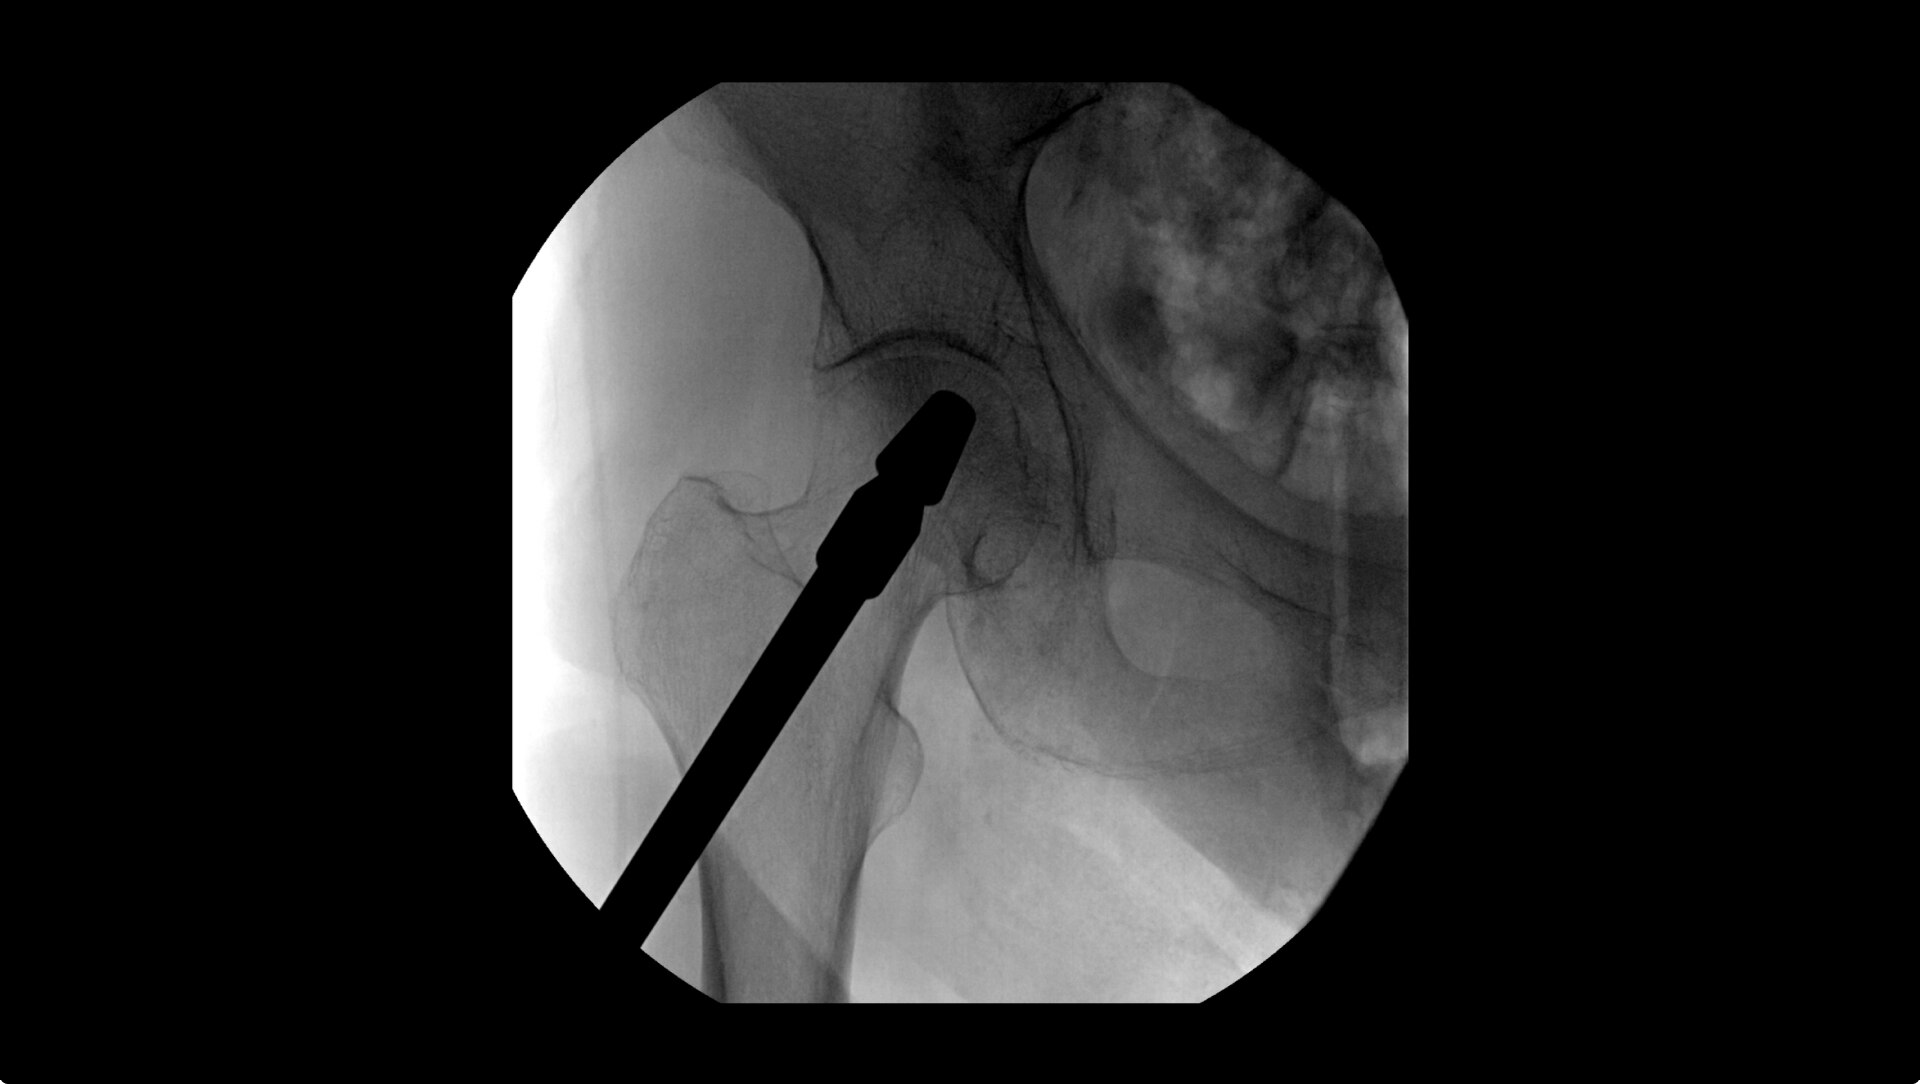

During hip or femur imaging, capture up to 22% more Field of View by positioning detector closer to patient anatomy with the OEC low-profile X-ray tube housing compared to mono-block C-arms.

Complex orthopedic procedures require powerful imaging systems. OEC premium C-arms perform in a variety of procedures such as:

• Hip fracture fixation

• Hip replacement

Mark right on the image displayed with Digital Pen, to template femoral and acetabular procedures and utilize measurement and angle tools for adding references for surgical planning.

Live Zoom up to 4X during a fluoro without the additional dose of Mag modes to assess orthopedic fractures and fixations.